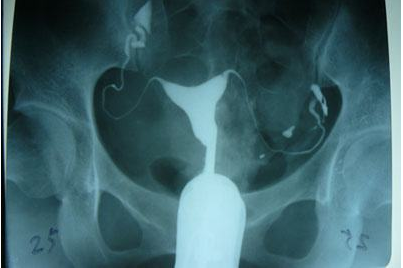

輸卵管造影是用來檢查女性輸卵管通暢與否的一種檢測方法。目前,輸卵管造影是臨床上應用較為廣泛的方法之一。造影是通過導管經陰道、宮頸、子宮腔直接插向子宮角的輸卵管開口處,對著輸卵管推注造影劑而使輸卵管顯影,進而了解輸卵管是否通暢、阻塞部位及宮腔形態的一種檢查方法。

輸卵管造影檢查可直觀了解輸卵管是否通暢以及阻塞的部位,觀察子宮腔的大小、形態、有無畸形及有無宮腔粘連或占位性病變,而且不孕不育專科醫院所采用的造影劑都是對人體沒有傷害可吸收的,對輕微的輸卵管堵塞患者還能疏通治療,可以在次月實施備孕。

推注造影劑力,造影劑進入盆腔緩慢,在停注造影劑數十分鐘后,可見造影劑在盆腔內彌散,但彌散欠佳。

輸卵管完全不顯影或顯影一段后不再顯影,且造影劑注入到一定劑量時阻力加大,盆腔內無造影劑影彌散。

造影劑積聚在輸卵管內,輸卵管常擴張呈囊狀或臘腸狀,以遠端明顯,多伴有輸卵管傘端阻塞。盆腔內一般無造影劑影彌散。